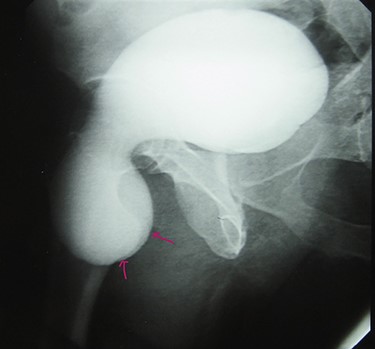

A 72-year-old man with a history of controlled diabetes and hypertension presented to our department with right inguinal swelling and intermittent lower urinary tract symptoms (LUTS) with pollakiuria, dysuria, prolonged micturition time and a sensation of a full bladder after micturition. He reported nausea, vomiting and right lower quadrant paint. The patient also reported having to manually compress the scrotum in order to empty the bladder. Physical examination revealed a slightly painful on palpation and reducible 6 cm right inguinal hernia extending into the right hemiscrotum. The body mass index of the patient was 31.4 kg/m2. His PSA was 4.3 ng/ml. On uroflowmetry, maximum flow rate (Qmax) was 13 ml/s and the voided volume was 180 cc. The uroflow curve was flat. The Bacteriological examination of urine was negative. Retrograde urethrocystography revealed right inguinal hernia containing a portion of the urinary bladder (Figs 1,2). He also had an intravenous urography in order to study the upper urinary tract and to have an idea of the renal function. This radiological exploration confirms the data of the retrograde urethrocystography and illustrates well the bladder hernia. However, a moderate left hydronephrosis with a nonobstructive pyelic calculus of 1.5 cm was observed on intravenous urography (Figs 3,4). Intraoperative findings revealed a direct right inguinal hernia with complete herniation of bladder into the scrotum. The bladder appeared healthy with no signs of injury and was restored to its normal anatomical position without resection. The hernia was repaired with a biologic mesh by the Lichtenstein technique. The patient had an uneventful postoperative course. Concerning his pyelic calculus problem, shock wave lithotripsy sessions were scheduled.

Retrograde urethrocystography: right inguinal hernia containing a portion of the urinary bladder.